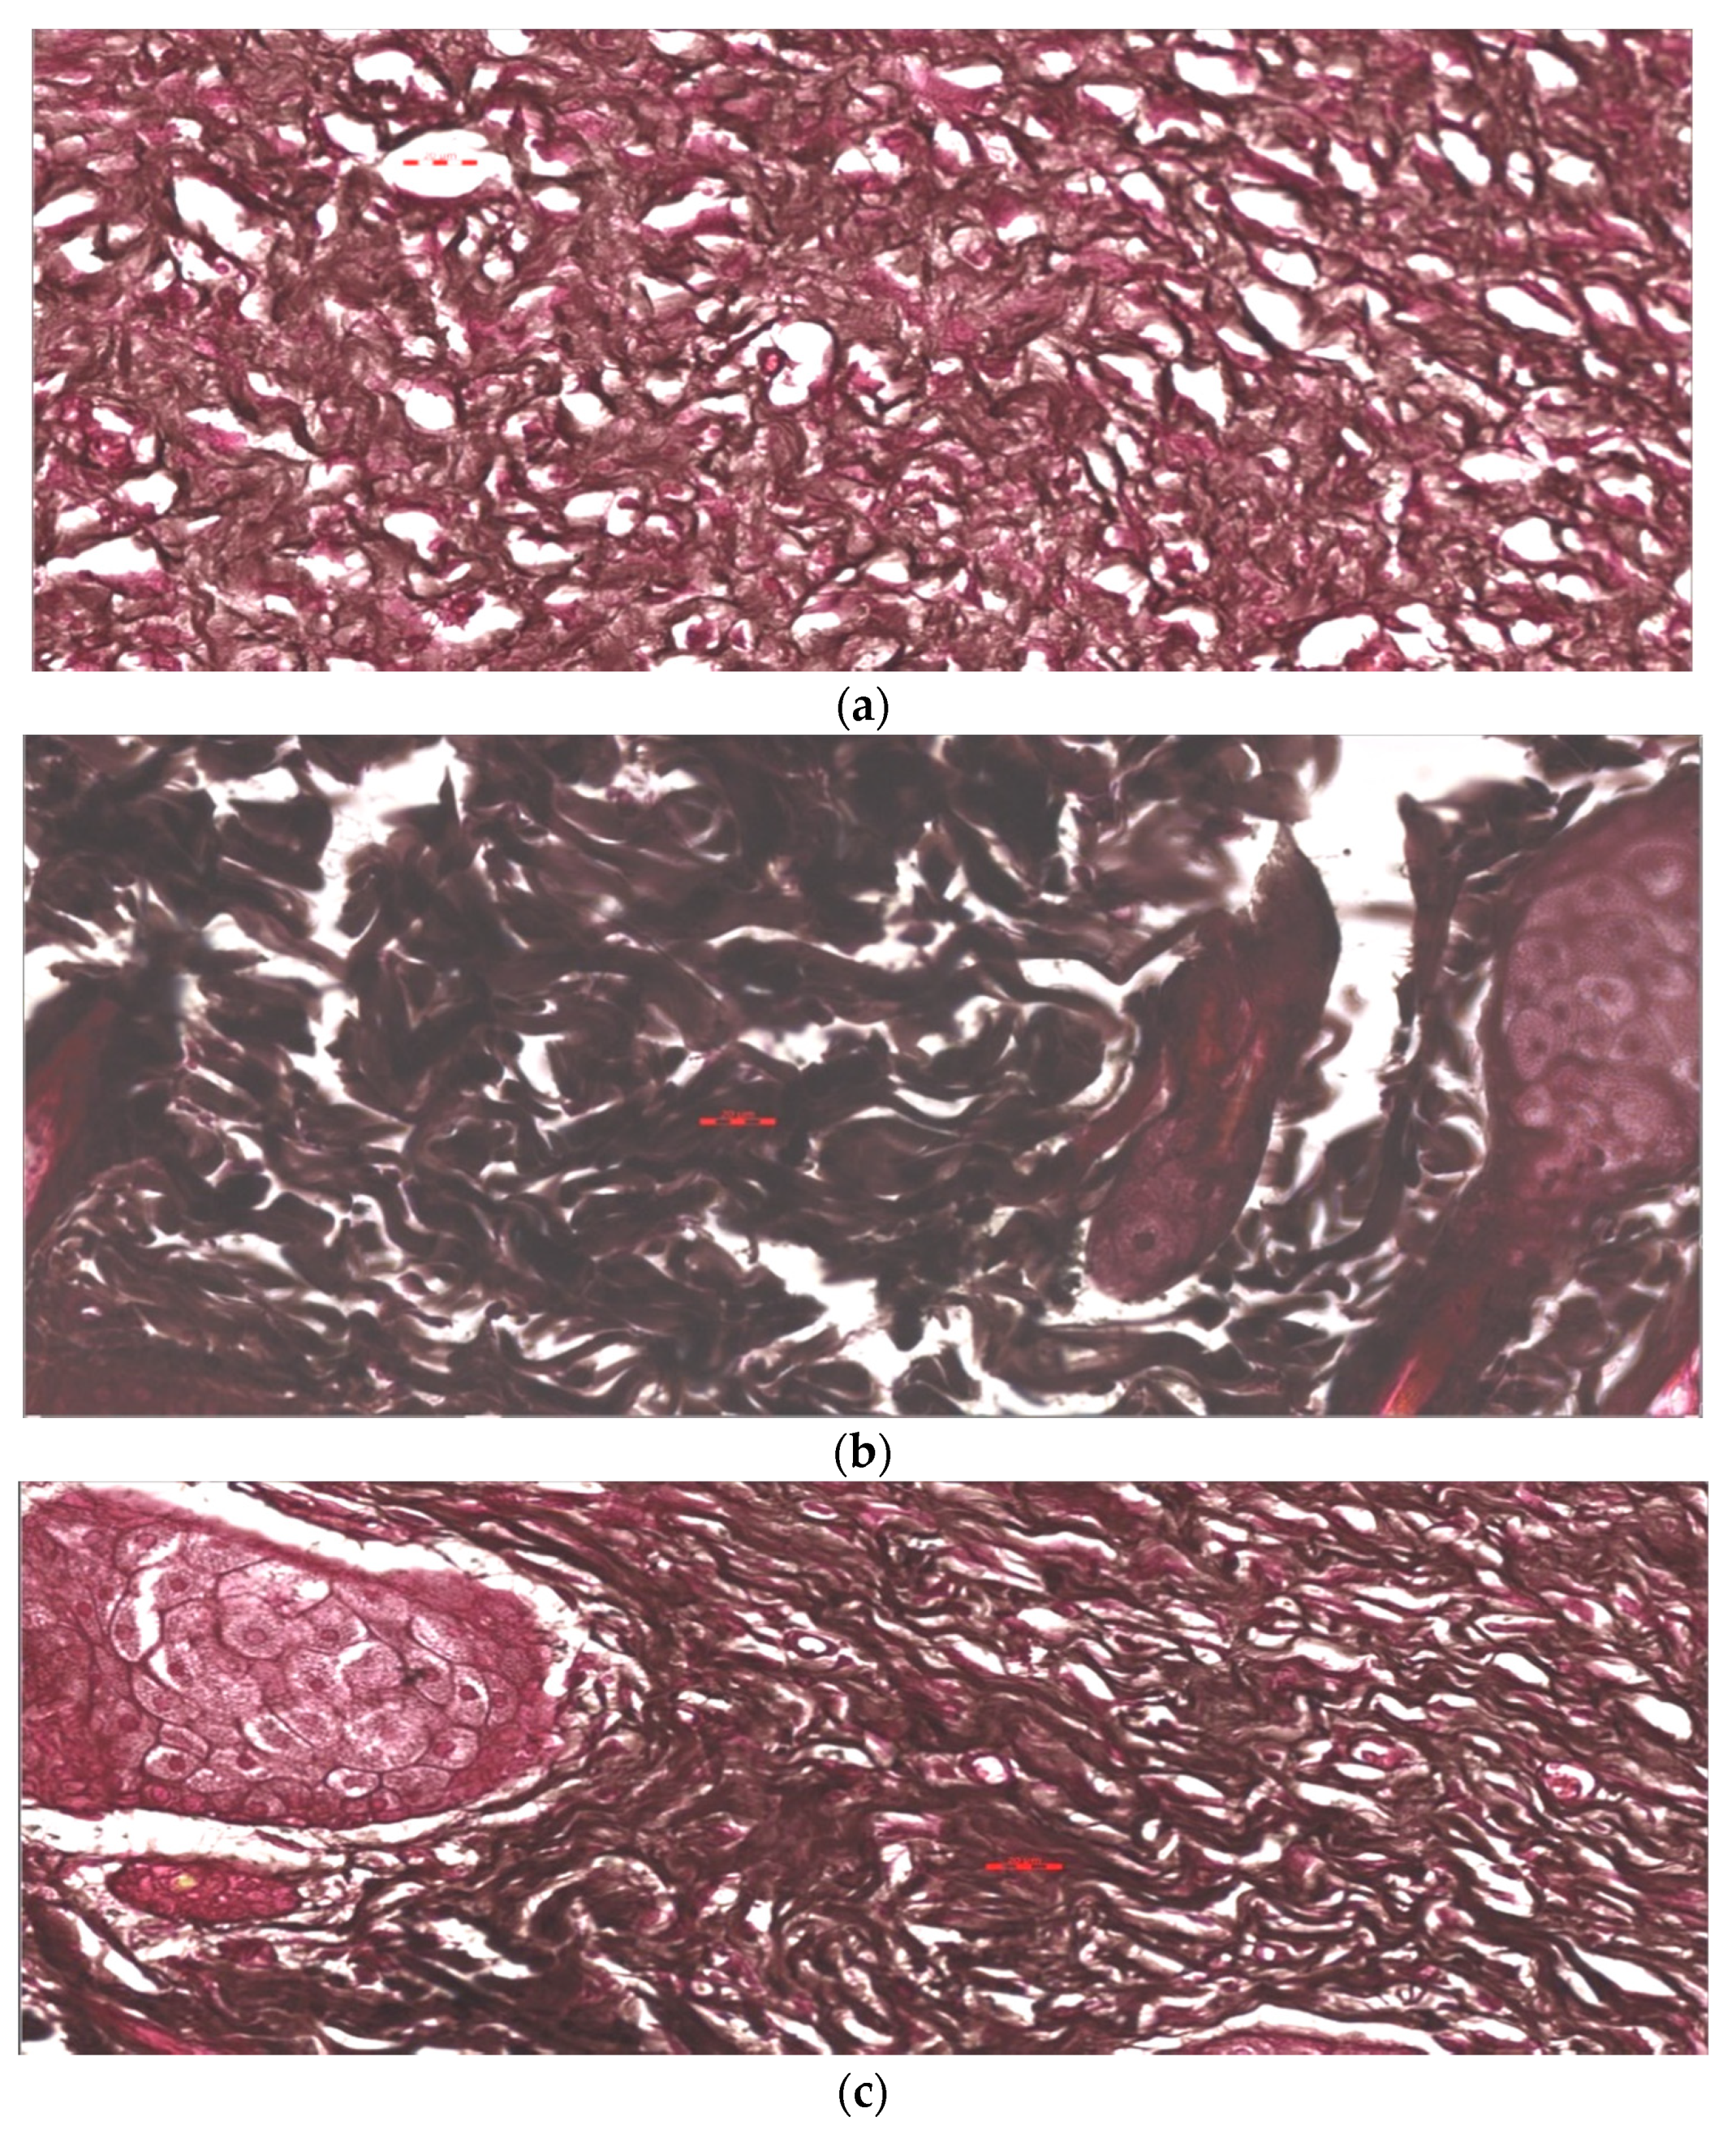

3.7. Histopathological Study